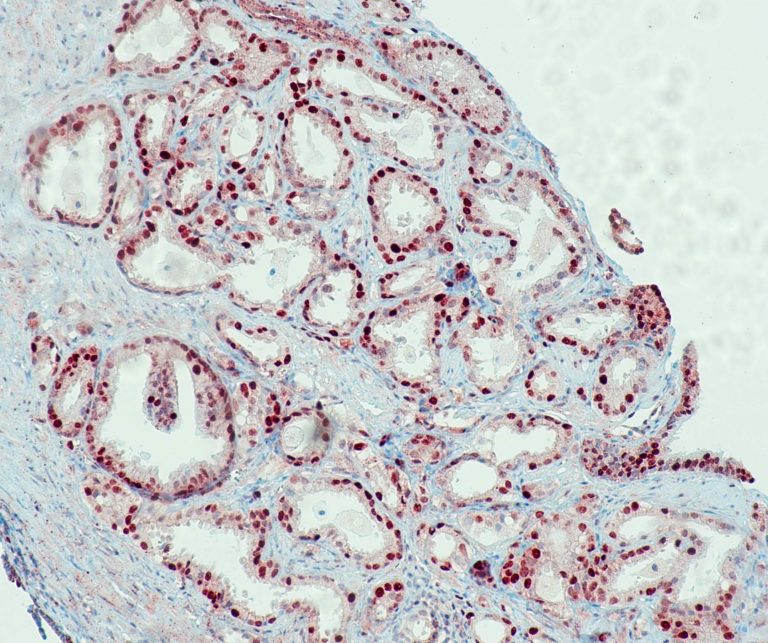

Vascular Pathology

Gastrointestinal (GI) Pathology

General Marker

Breast Pathology

Endocrine Pathology

Gynecological Pathology

Neuropathology

Infection Markers

Lung Pathology

Urinary Tract Pathology

Transplantation Pathology

Soft Tissue Pathology

Hematopathology